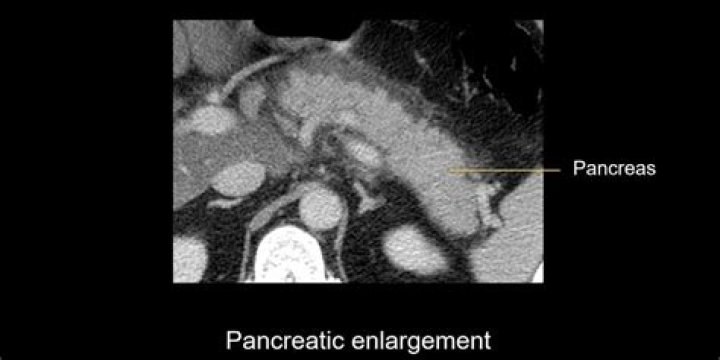

Necrotizing pancreatitis (NP) is a health problem in which part of your pancreas dies. This is because of inflammation or injury. If the dead tissue gets infected, it can cause serious issues. The pancreas is an organ that sits behind your stomach.

NP happens when your pancreas gets inflamed or injured, and the pancreatic enzymes leak. This harms the tissues of the pancreas. If this damage cannot be reversed, it causes NP. In some cases, the nearby tissue may become infected.